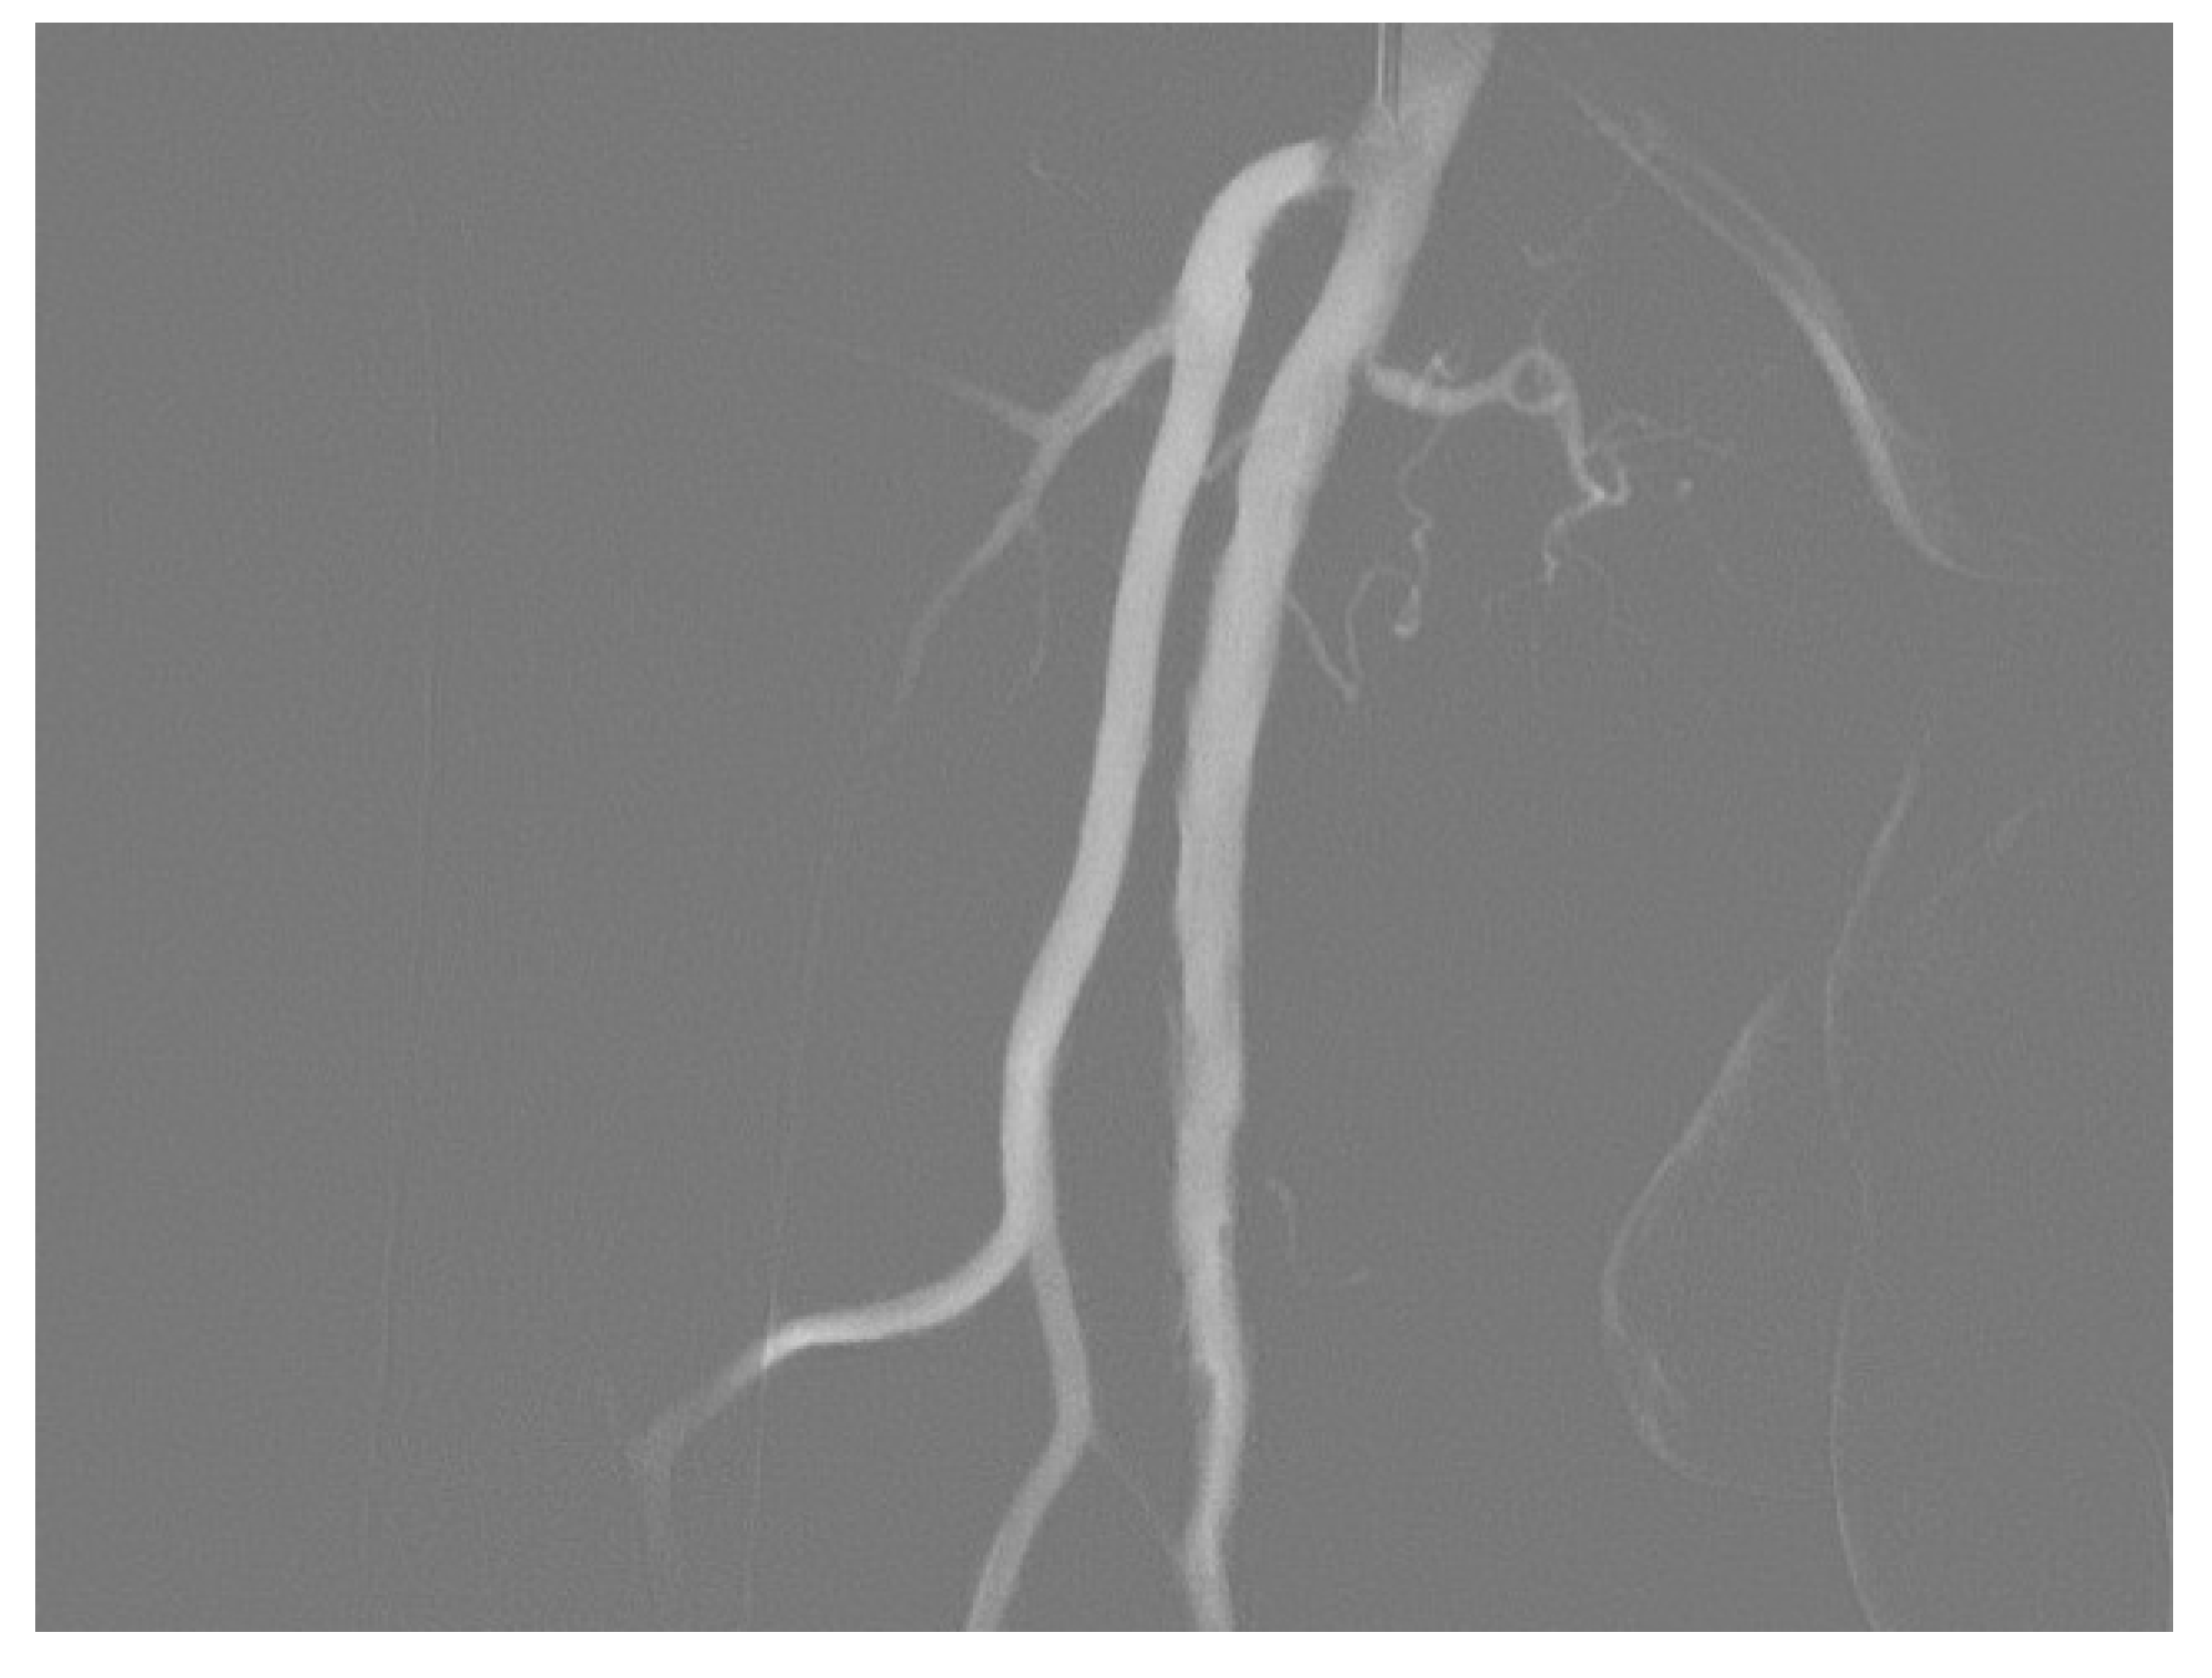

3.1. Stenosis and Occlusion